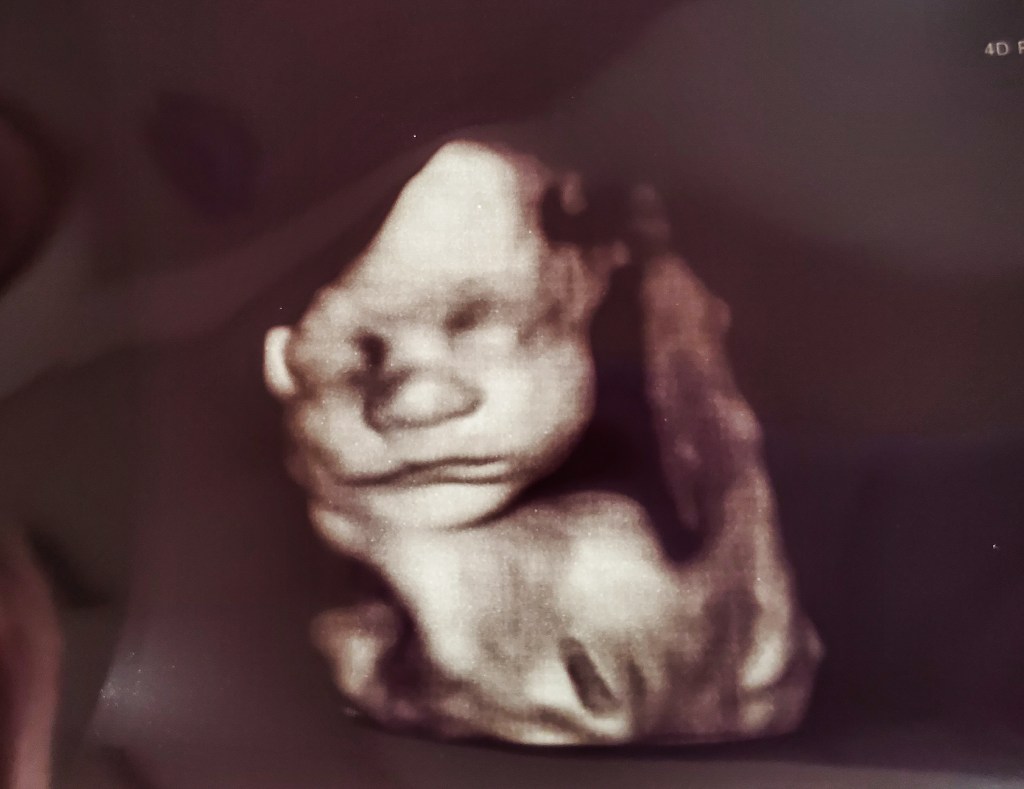

For your amusement. A few pictures of me throughout this pregnancy.

Things escalated quickly in the belly department.